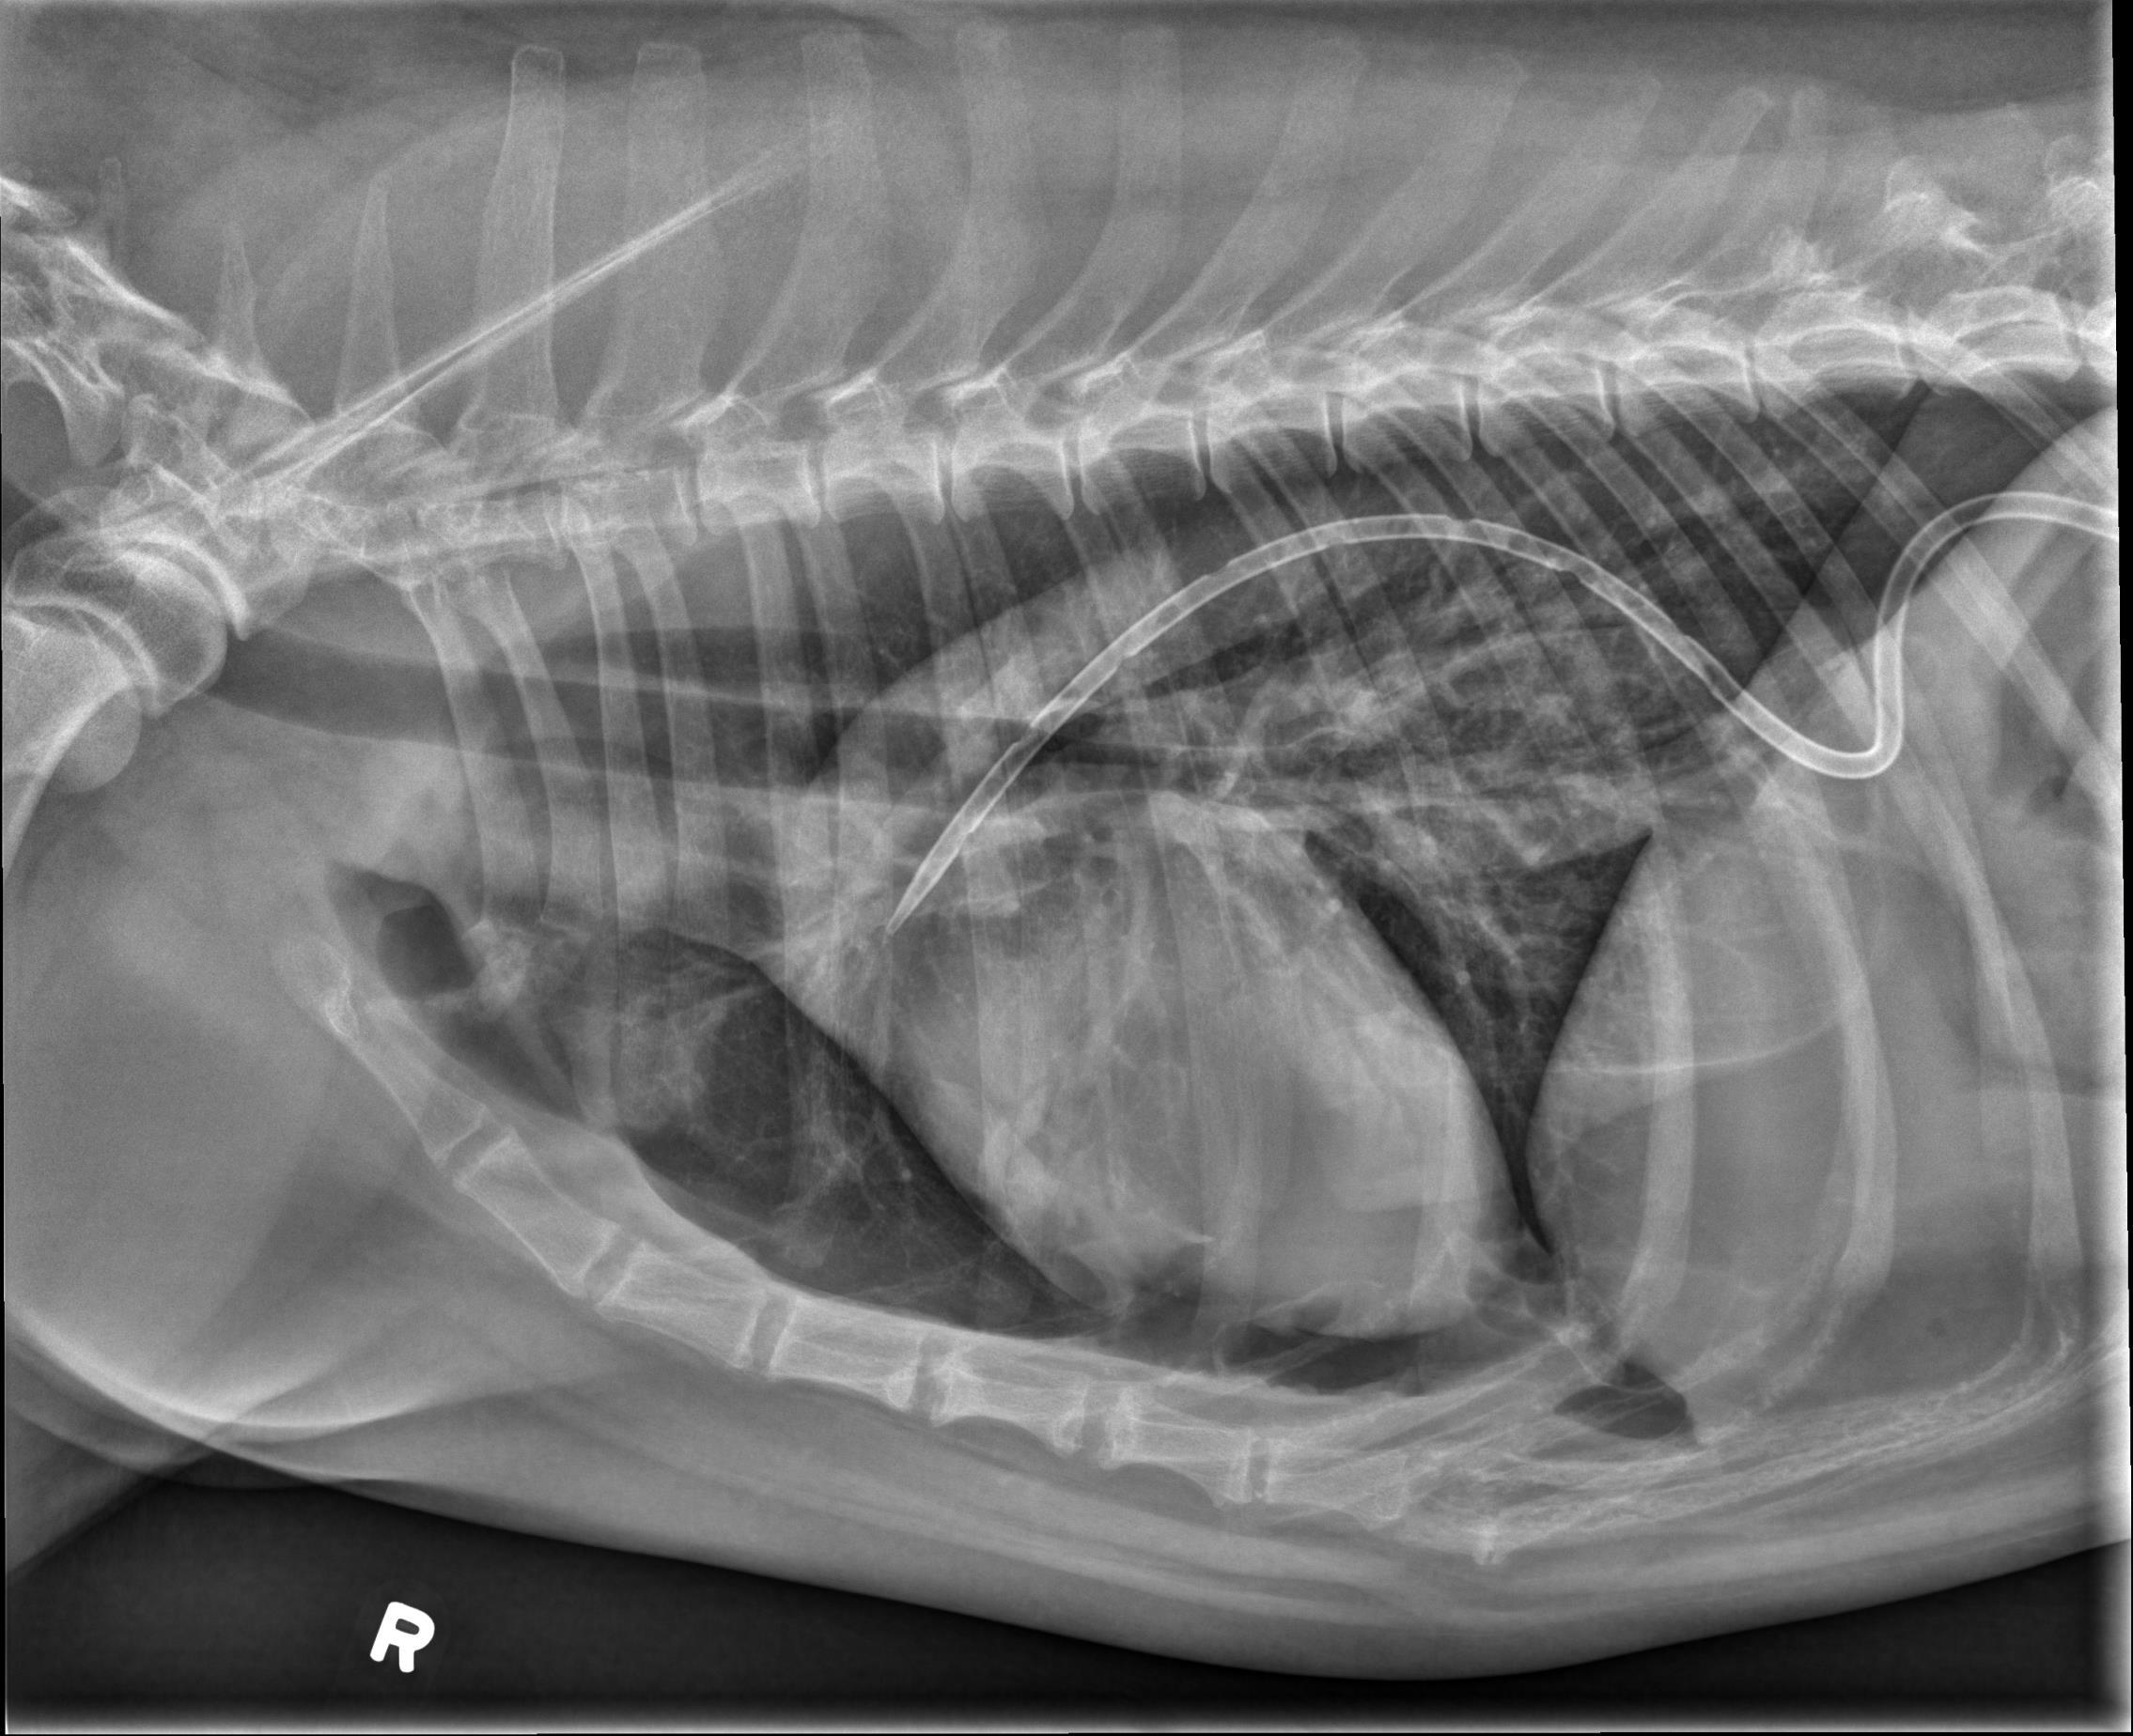

2犬猫胸腔积液和肺水肿的X光片诊断阅读 (1945)